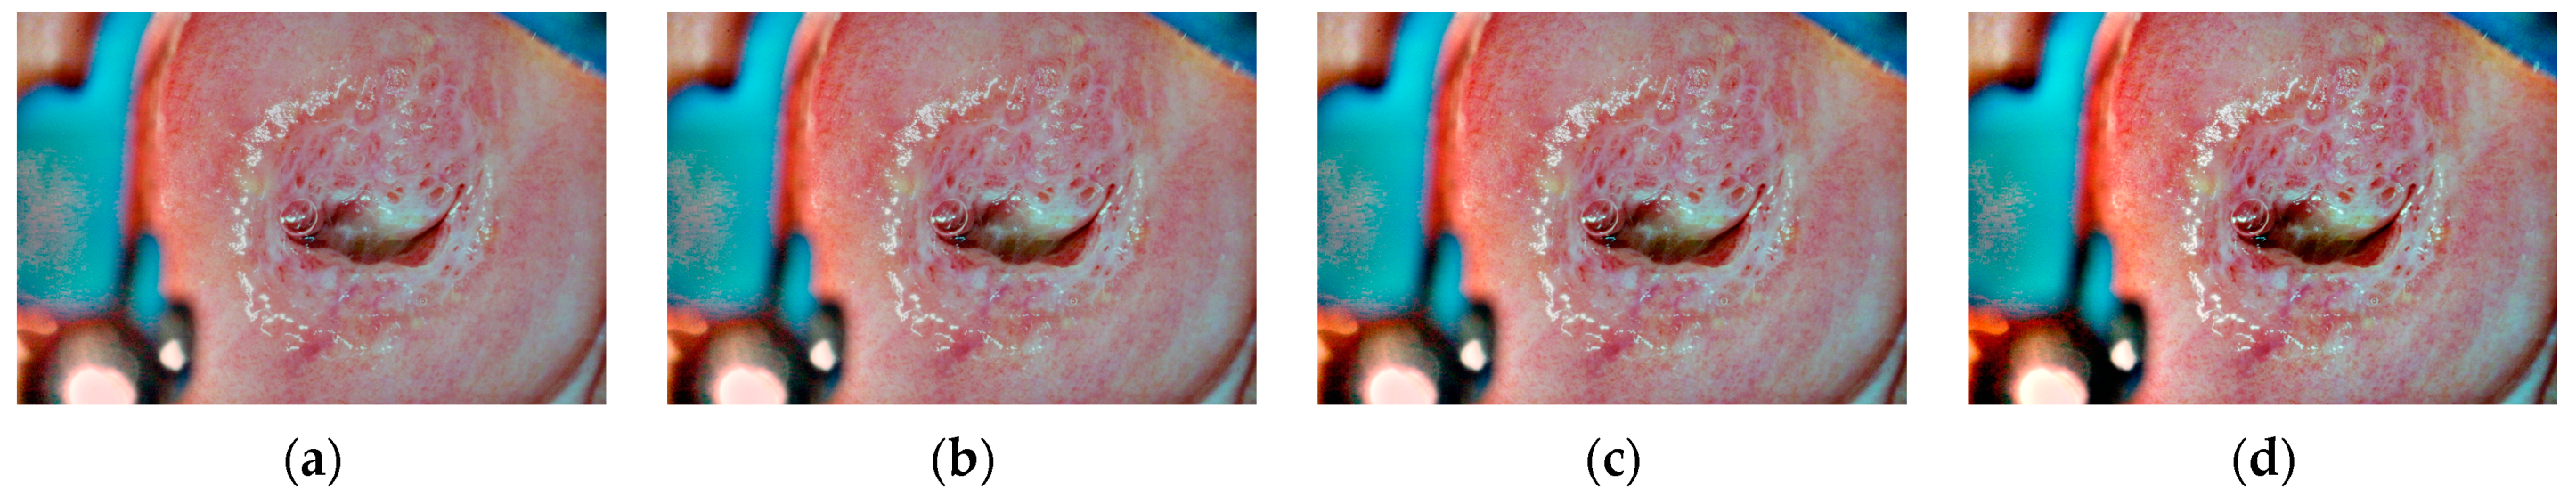

- This paper selectively applies the contrast-limited adaptive histogram equalization (CLAHE) algorithm to the blue and green channels, which contain more detailed information, to improve the contrast between lesion areas and the background without excessive enhancement.

4.3. Subjective and Objective Evaluation